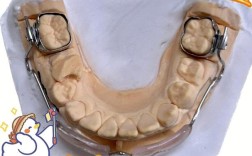

- 第一阶段(6个月):戴用上颌螺旋扩弓器( expansion screw,每天加力1次,每次0.25mm,扩弓至尖牙间宽度32mm),同时配合前方牵引面具(牵引方向与牙合平面呈30°,牵引力300g/侧,每天佩戴14小时),治疗后,上颌牙弓宽度增加,前牙反覆盖改善至1mm,磨牙关系转为中性偏近中。